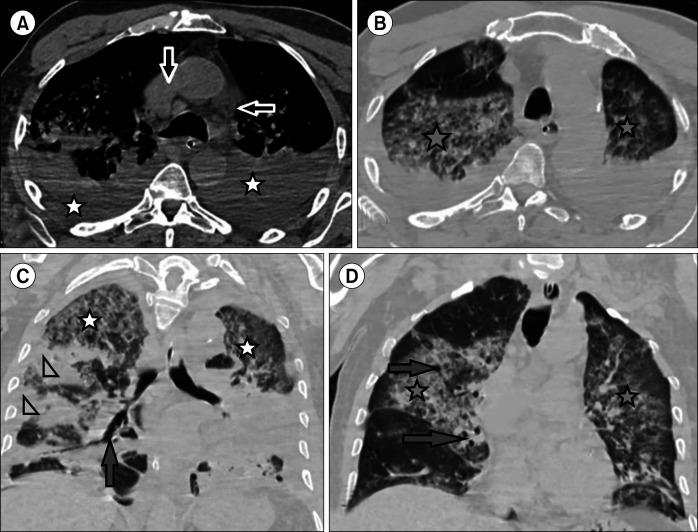

Data on the association between coronavirus disease 2019 (COVID-19) and the epidemiology and outcomes of hematological malignancies are limited. Hence, the present study aimed to assess the imaging findings using chest multidetector computed tomography (MDCT) in patients with hematologic malignancies who developed COVID-19 pneumonia.

This retrospective study included two groups, the first group consisted of COVID-19 infected patients with hematologic malignancies (100 patients), while the second group consisted of COVID-19 infected patients without hematologic malignancies or other comorbidities (100 patients). The hematological malignancies included in this study were non-Hodgkin's lymphoma (40 patients), acute myeloid leukemia (25 patients), chronic lymphocytic leukemia (15 patients), multiple myeloma (10 patients), Hodgkin's lymphoma (8 patients), and myelodysplastic syndrome (2 patients). Chest multidetector CT imaging was performed in all patients to assess for ground-glass opacity, consolidation, pleural effusion, and airway abnormalities.

More than one CT finding was reported in each patient. No significant difference was observed in the ground-glass opacities (=0.0594), nodule formation (=0.2278), or airway thickening/dilatation (=0.0566) between the two groups; meanwhile, a significant difference was observed in the degree of consolidation, the number of lobes affected, and pleural effusion (=0.0001) as well as in the total lung severity (=0.0001); minimal, mild, and severe affection rates; and (=0.0047) moderate affection rates.

Early and reliable diagnosis of lung disease in COVID-19-infected patients may be achieved through multidetector CT imaging. Patients with hematological malignancies are more likely to have severe COVID-19 pneumonia, and radiologists should recognize the CT characteristics of this infection.